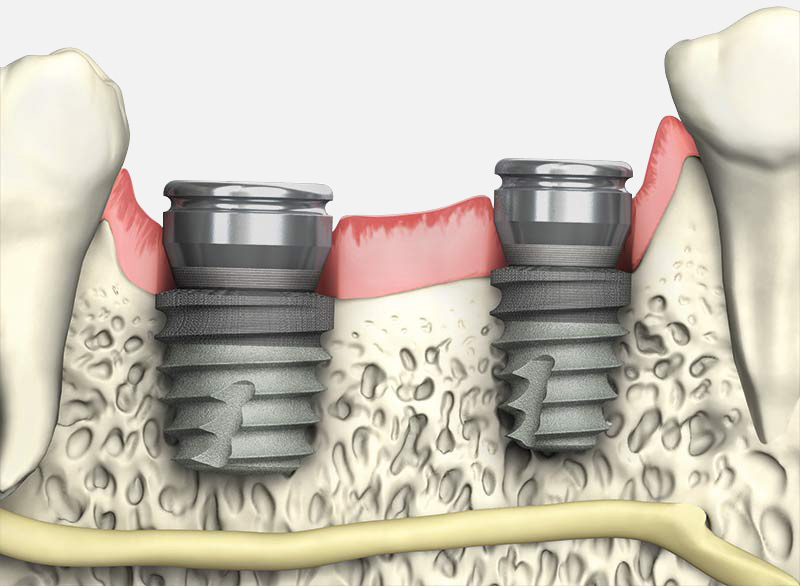

Xüsusilə irəli dərəcə vertikal sümük əksiklikliyi olan durumlarda normal ölçülü diş implantlarının tətbiqi üst çənə arxa bölgələrdə haymor boşluğu dibinin perforasiyasına (deşilməsinə), alt çənə arxa bölgədə isə çənə sinirinin zədələnməsinə səbəb ola bilər. Belə durumlarda normal ölçülü implantların tətbiqi üçün öncə sümük köçürməsi icra edilərək sümük hündürlüyü yetərli səviyyəyə çatdırılmalı daha sonra isə implantasiya icra edilməlidir. Bu isə daha uzun müalicə müddəti, daha yüksək maliyyət və daha böyük bir və ya bir neçə cərrahi prosedurla həyata keçirilir. Qısa implantlar məhz belə durumlarda həm cərrah-implantoloqlar həm də pasiyentlər üçün çox yaxşı bir müalicə alternativi ola bilər. İcra olunduqda belə dişsiz bölgəyə müvafiq implant sayıının, pozisiyasının və sonrakı mərhələdə hazırlanacaq diş növünün də nəzərə alınması uğurlu nəticə üçün olduqca əhəmiyyətlidir.

Qısa implantların sxematik və rentgenoloji görünüşü